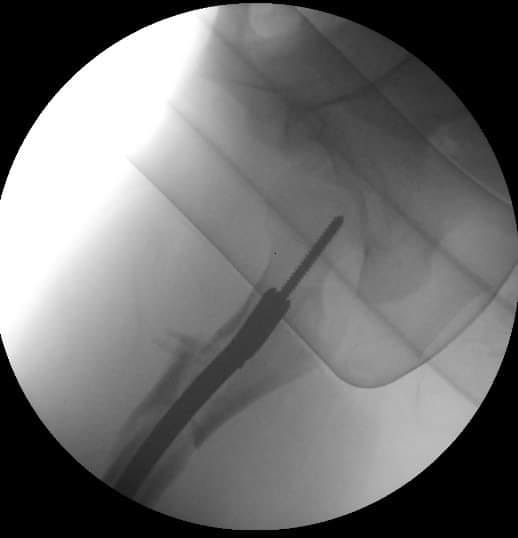

[Ortho] Перелом бедра, девочка 11 лет

Вот, что получилось.

Имя     : 1.jpg